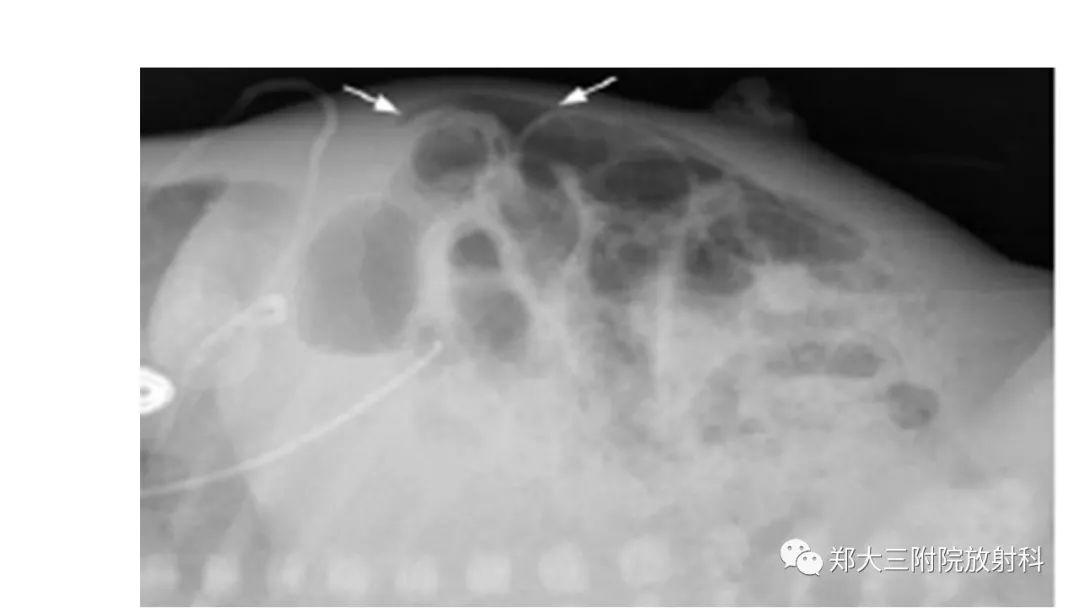

医学百科网 | YxBaike.Com •NEC(necrotizing enterocolitis)是一种获得性的新生儿肠功能紊乱,是由于发育不全的肠壁黏膜、血管受到缺血、感染、代谢等因素联合作用的刺激,导致严重肠损伤。NNEC是新生儿最常见的需急诊手术的肠道疾病。

•NEC多见于生后2-3周,以早产儿、低体重儿、人工喂养儿多见,特别是胎膜早破产程延长或出生时有窒息的新生儿。•早期即可有腹胀、肠鸣音减弱或消失。•呕吐,呕吐物可呈咖啡样或含有胆汁。•血便,常呈洗肉水样,量较多,腥臭。腹泻,体温不稳定,精神反应差,拒食。

•NEC特征性的影像表现主要为肠壁积气及门静脉积气,如果临床上患儿有腹胀、血便、肠鸣音消失等病史,应高度怀疑NEC的可能。 医学百科网 | YxBaike.Com